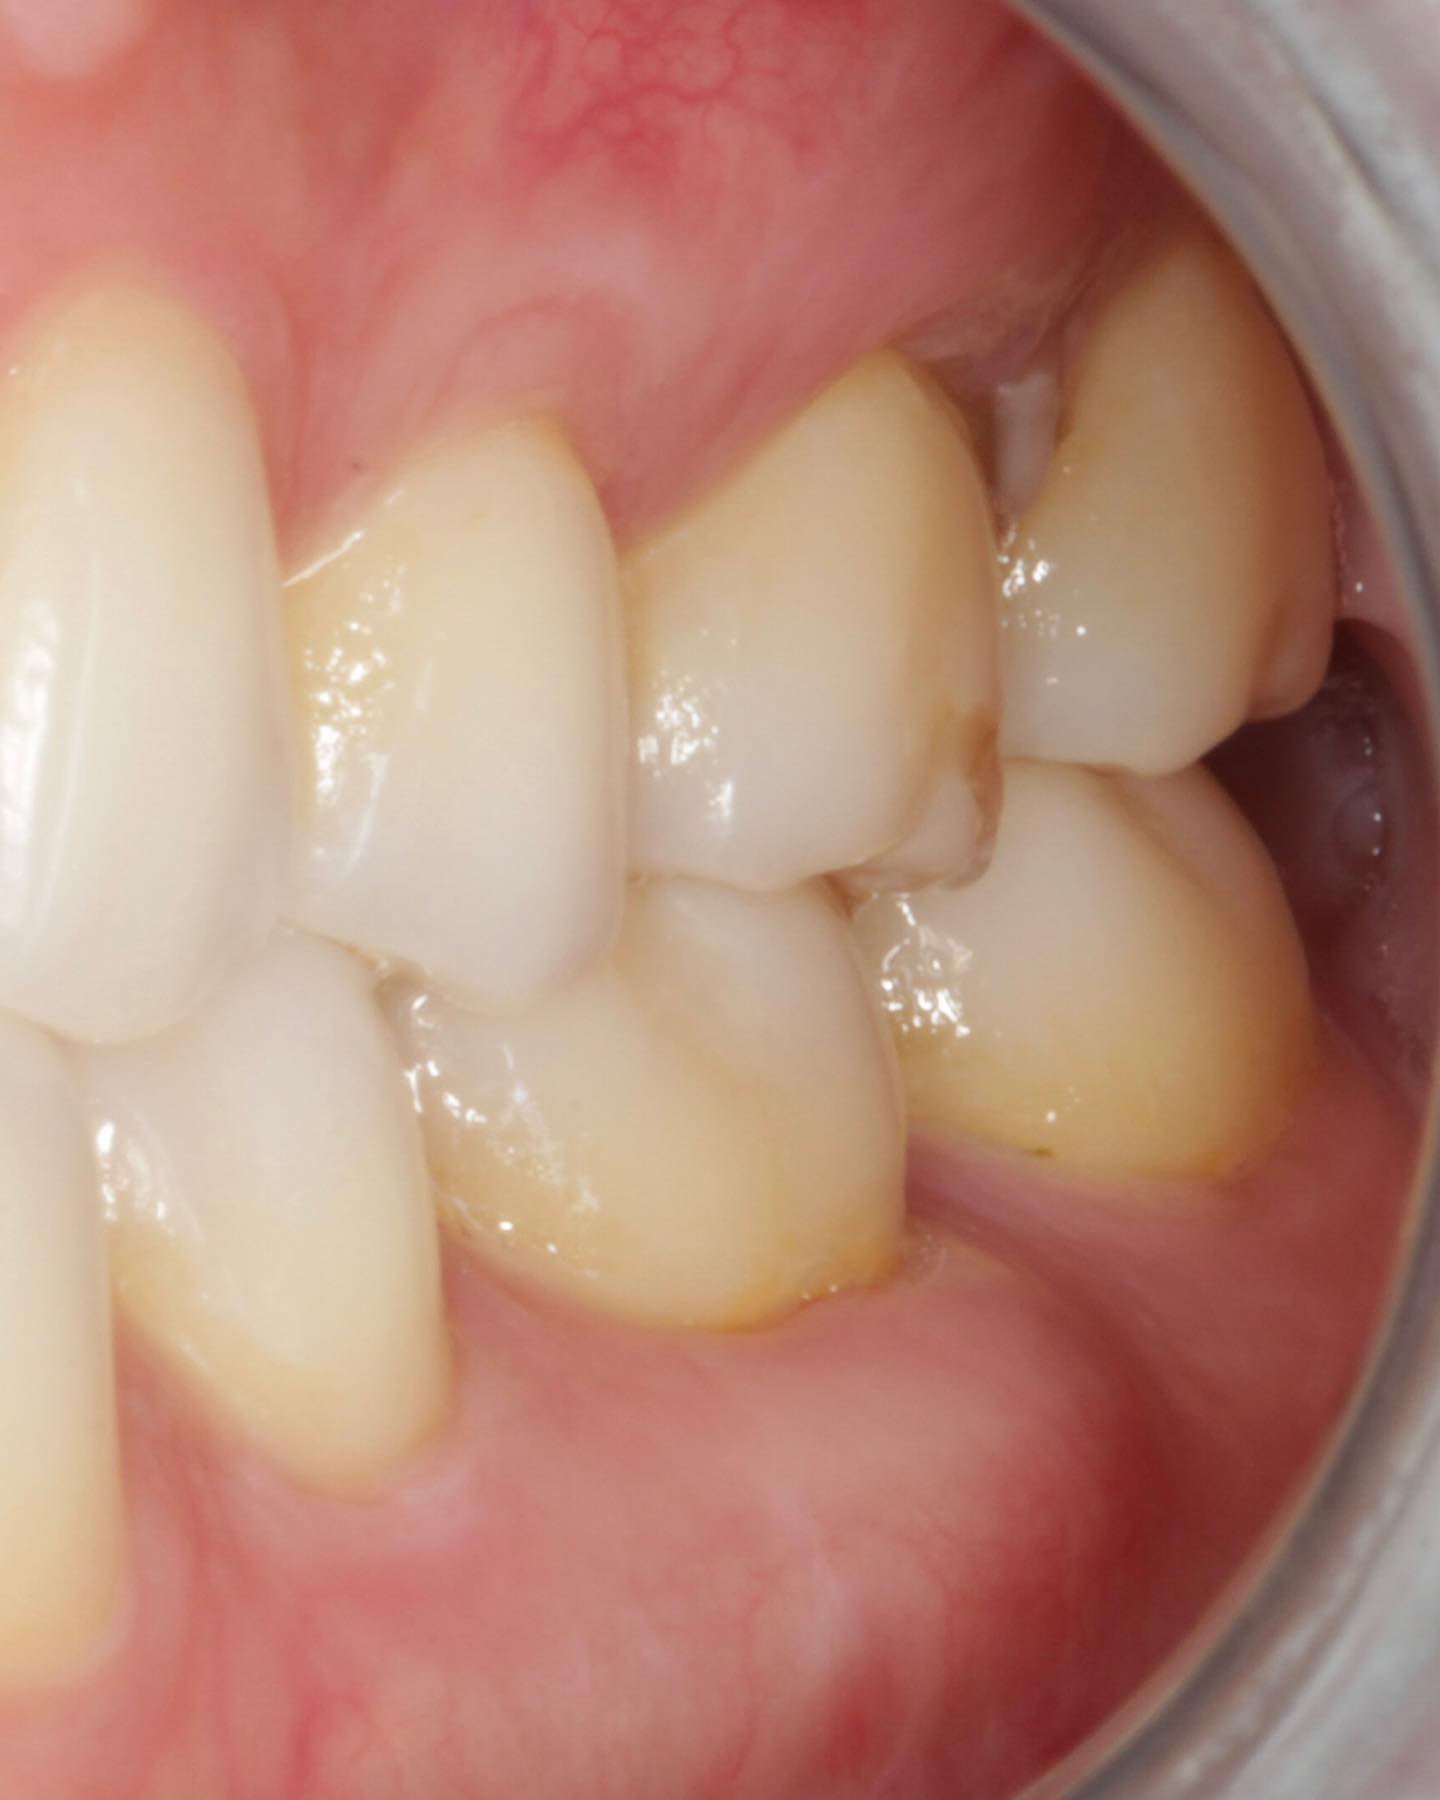

Immediate Implant Placement in Molar Extraction Site

IMPrESS Perio Implant Center Dr. Noroozi Vancouver Periodontist Implant Specialist Burnaby BC

immediate implant placement in molar site Dr. Noroozi